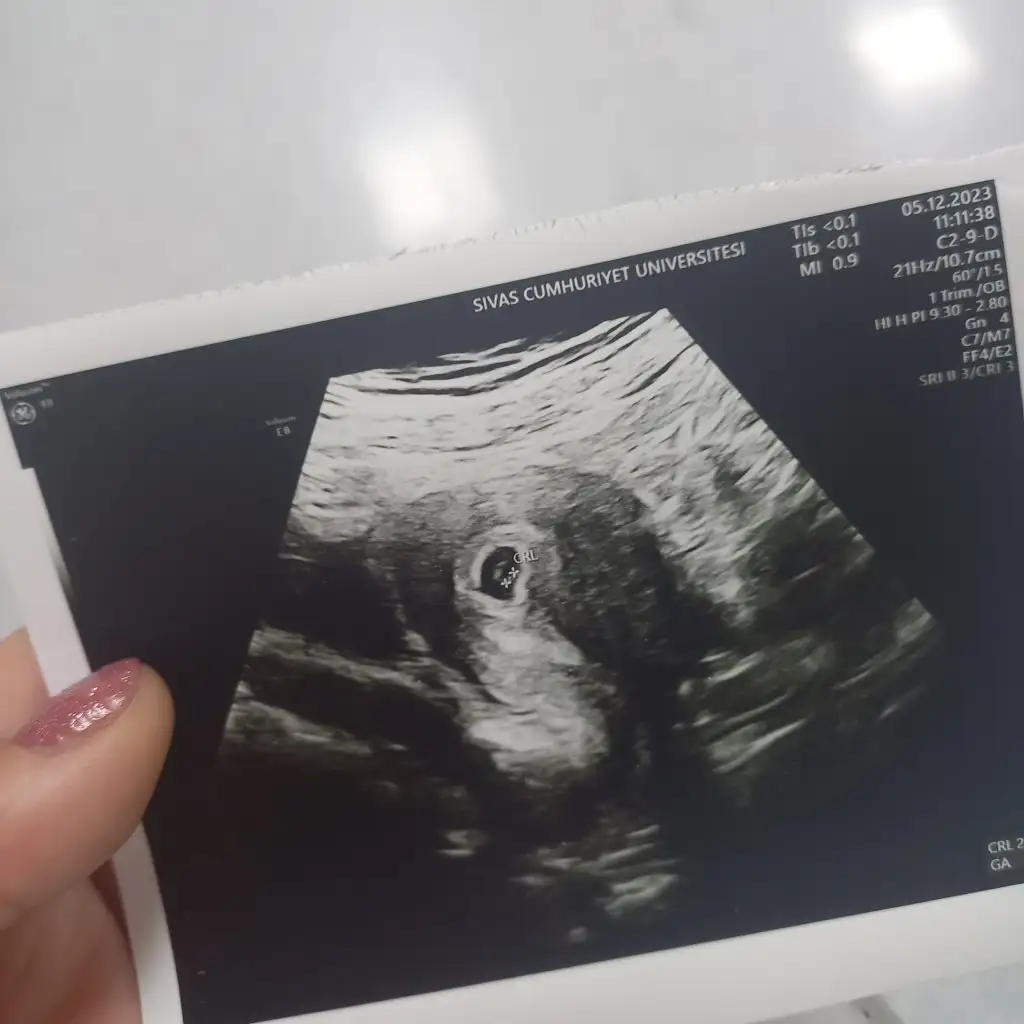

bende de bugun gozuktu minnak bi kese :) biz secmiyorduk da biri gonullu oluyordu . yani 2019 yilinda oyleydi , simdi sistem degisti mi bilmiyorum :)Sınıf başkanı mı seçeceğizmerak ediyorum kese gören var mı diye de :)

Görmüşsün keseyi hadi gözün aydın canımcanim dr dan ciktim , keseyi gordu sadece 5+2 dedi daha , haftaya kalp atisi icin randevu verdi insallah saglikli bir gebeliktir

Günaydın canım bebişi gördü mü pekicanim dr dan ciktim , keseyi gordu sadece 5+2 dedi daha , haftaya kalp atisi icin randevu verdi insallah saglikli bir gebeliktir

Gözün aydın canım sağlıklıdır eminim zaten doktor riskli görse direk söylüyorcanim dr dan ciktim , keseyi gordu sadece 5+2 dedi daha , haftaya kalp atisi icin randevu verdi insallah saglikli bir gebeliktir

Maşallah Rabbim kucağına almayı nasip etsin. Kese ve bebeğin bu hafta da görülmesi beta hcg değeri ile orantılı mı acaba? Benim diğer gebeliğimde bu haftada görülmemişti. Bu sefer de diğeri gibi yavaş ilerliyor görülmez sanırımKızlar Günaydın ben bugün hastaneye tekrar gittim devlet hastanesine 5+5 ve bebisi gördük şükür darısı hepinize